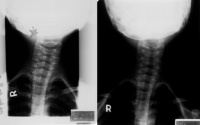

斜颈

2、X线检查,有利于鉴别不同原因造成的斜颈,如枕颈部畸形所致的骨性斜颈和自发性寰椎旋转性半脱位引起的斜颈一般不会产生胸锁乳突肌的挛缩和肿块,后者多有轻微外伤上呼吸道感染病史。